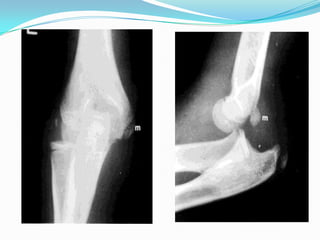

EVALUACION RADIOLOGICA

 Proyecciones AP y Lateral del codo.

 Deben evaluarse posibles fracturas asociadas a la

articulacion del codo

La rayos X AP y lateral es

imperativa para confirmar

el diagnóstico y descartar

fracturas asociadas